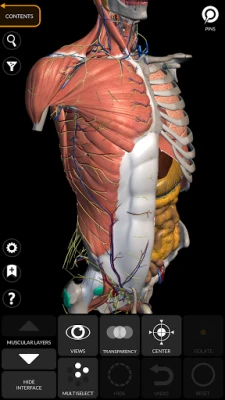

"Anatomy 3D Atlas" allows you to study human anatomy in an easy and interactive way.

Through a simple and intuitive interface it is possible to observe every anatomical structure from any angle.

The anatomical 3D models are particularly detailed and with textures up to 4k resolution.

The subdivision by regions and the predefined views facilitate the observation and the study of single parts or groups of systems and the relationships between different organs.

"Anatomy - 3D Atlas" is an application aimed at medical students, doctors, physiotherapists, paramedics, nurses, athletic trainers and in anyone interested in deepening their knowledge of human anatomy.

This app is a fantastic tool to complement classic human anatomy books.

ANATOMICAL 3D MODELS

• Musculoskeletal system

• Cardiovascular system

• Nervous system

• Respiratory System

• Digestive System

• Urogenital system (male and female)

• Endocrine system

• Lymphatic system

• Eye and ear system

FEATURES

• Simple and intuitive interface

• Rotate and zoom each model in 3D space

• Option to hide or isolate single or multiple selected models

• Filter to hide or display each system

• Search function to easily find every anatomical part

• Bookmark function to save custom views

• Smart rotation which moves the center of rotation automatically

• Transparency function

• Visualization of muscles through levels of layers from the superficial ones down to the deepest ones

• By selecting a model or a pin, the related anatomical term shows up

• Description of the muscles: origin, insertion, innervation and action

• Show/Hide UI interface (very useful with small screens)